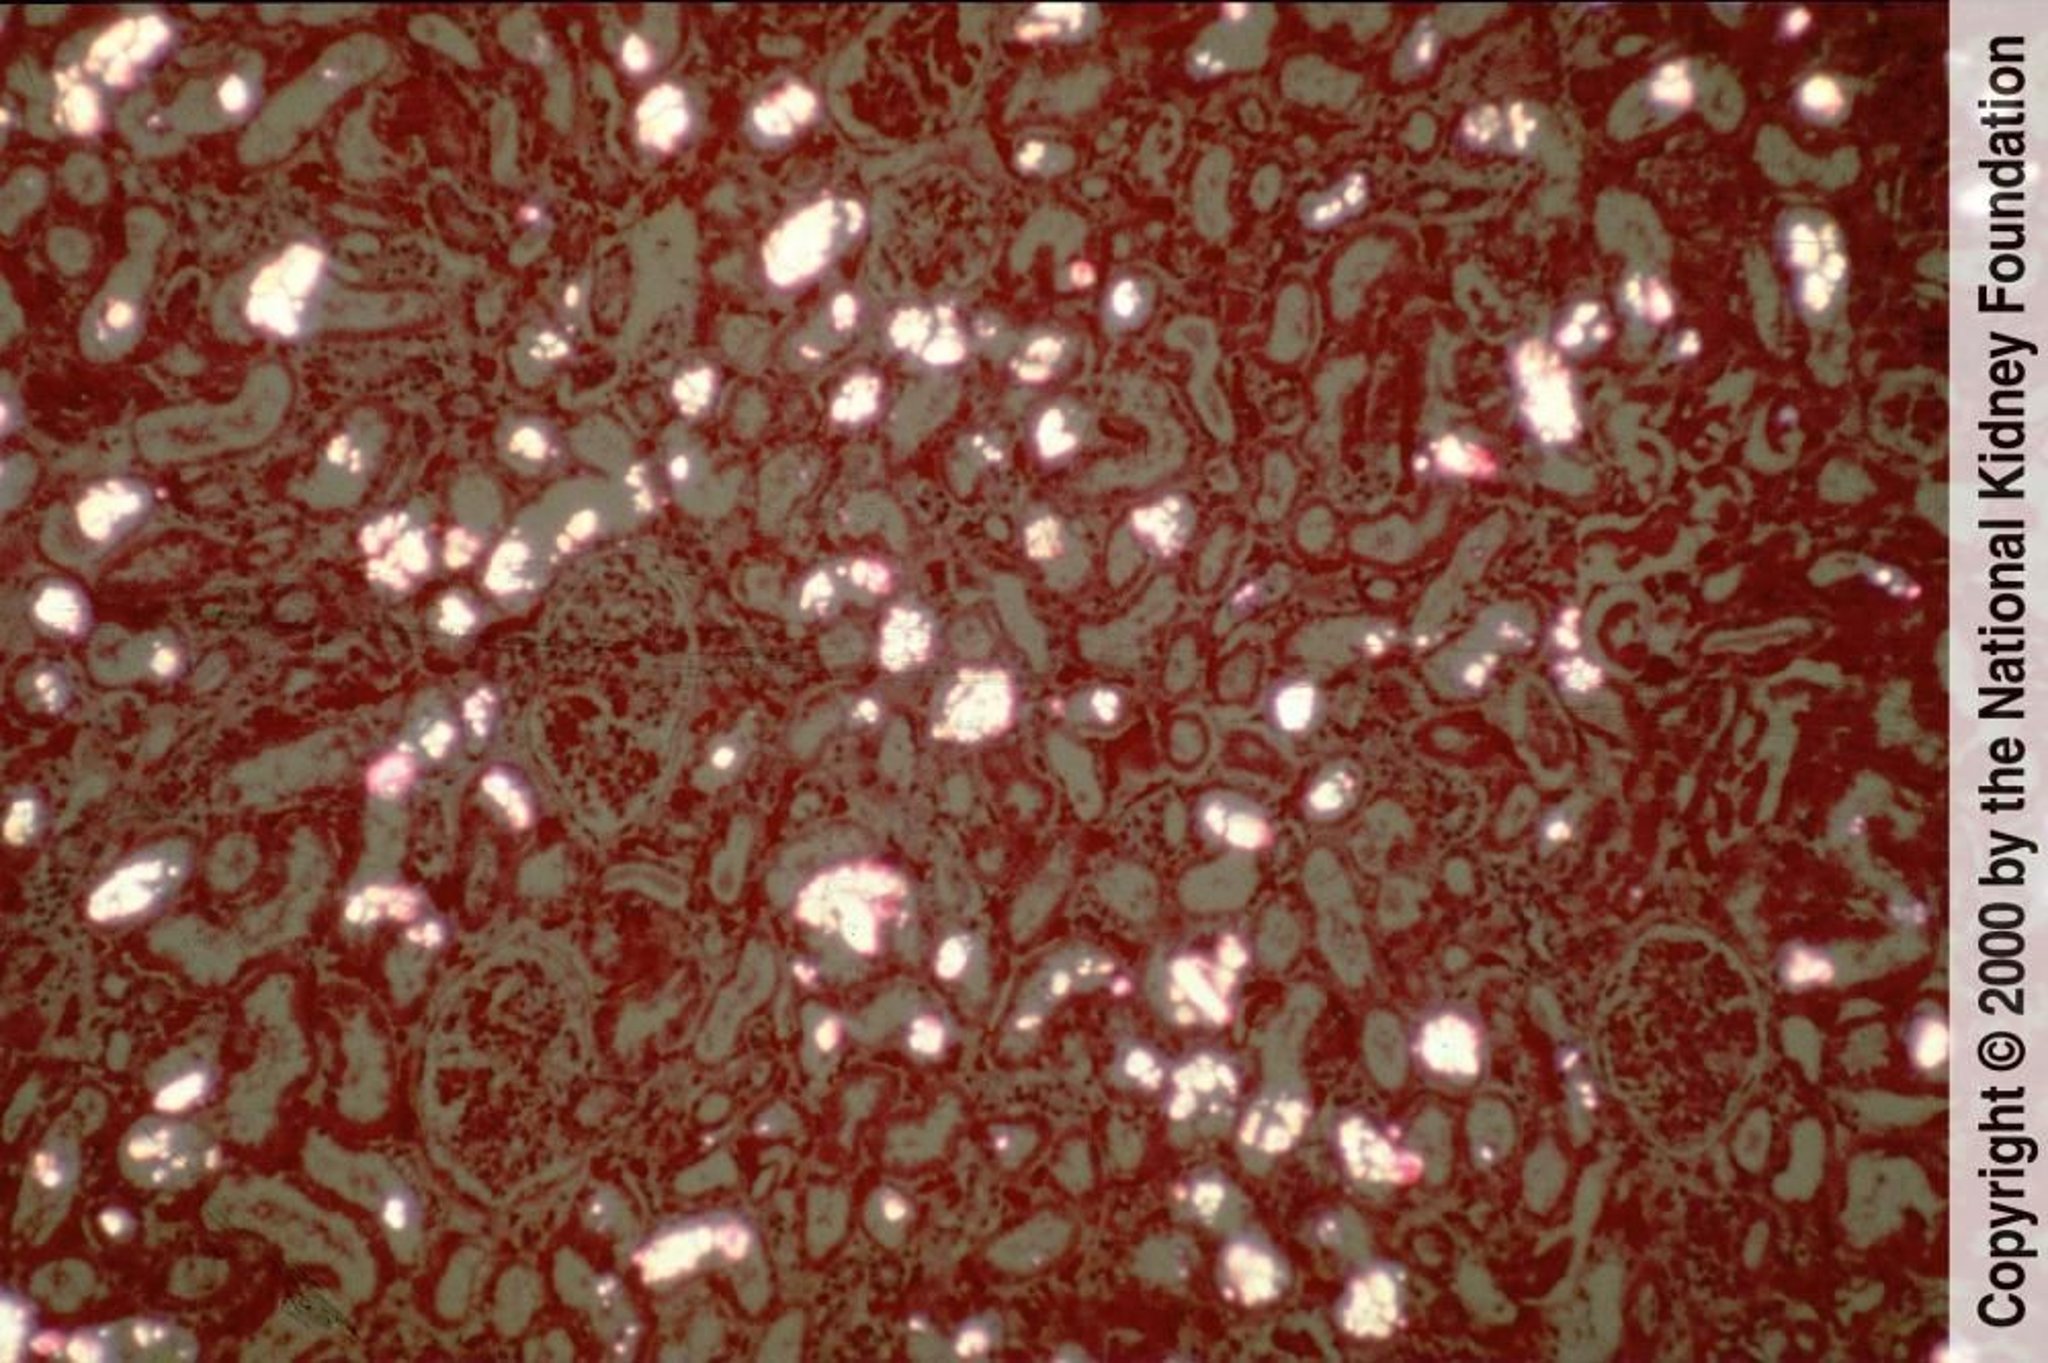

Les cristaux d'oxalate de calcium précipitent dans les tubules rénaux et sont bien visibles sous forme de cristaux biréfringents et en forme d'éventail en lumière polarisée (coloration polarisée à l'hématoxyline-éosine, ×100).

Image fournie par Agnes Fogo, MD, and the American Journal of Kidney Diseases' Atlas of Renal Pathology (voir www.ajkd.org).